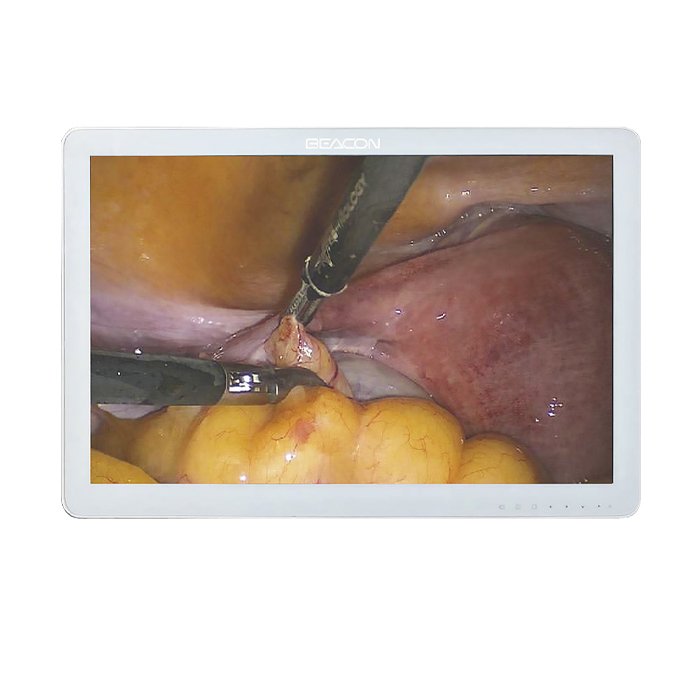

Монитор для эндоскопа 24 дюйма Huger

Монитор для эндоскопа 24 дюйма Huger: профессиональное решение для медицинской визуализации

В современной эндоскопии качество изображения напрямую влияет на точность диагностики и безопасность процедур. Монитор для эндоскопа 24 дюйма Huger — это специализированное оборудование, разработанное для работы в операционных, процедурных кабинетах и отделениях эндоскопии. Он обеспечивает четкую передачу деталей, что критически важно при проведении малоинвазивных вмешательств.

Монитор Huger 24 дюйма создан для длительной профессиональной нагрузки. Он сочетает в себе высокую яркость, контрастность и стабильность цветопередачи, что позволяет врачу не отвлекаться на технические артефакты и полностью сосредоточиться на работе с пациентом.

При выборе монитора для эндоскопии важно учитывать не только размер экрана, но и его способность корректно отображать мелкие структуры и оттенки тканей. Модель Huger 24 дюйма отвечает этим требованиям благодаря продуманной конструкции и качественной матрице.

- Диагональ 24 дюйма обеспечивает комфортный обзор без необходимости приближаться к экрану, снижая нагрузку на зрение хирурга.

- Высокое разрешение позволяет видеть мельчайшие детали эндоскопической картины, что особенно важно при работе с тонкими инструментами.

- Специализированная цветовая калибровка помогает точно различать здоровые и патологически измененные ткани.

Благодаря антибликовому покрытию экрана изображение остается читаемым даже при ярком освещении операционной. Это снижает риск ошибок, связанных с бликами и отражениями. Углы обзора достаточны для того, чтобы ассистенты и медсестры также могли видеть ход процедуры без искажений.

Ответ: Да, монитор Huger 24 дюйма с разрешением Full HD и IPS-матрицей обеспечивает достаточную детализацию для лапароскопии, гистероскопии, артроскопии и других эндоскопических вмешательств.